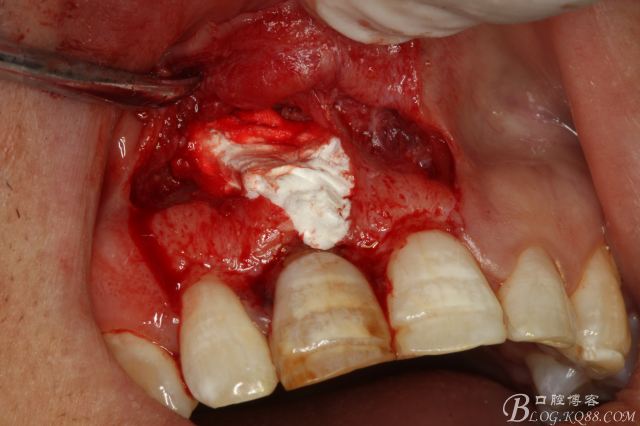

圖6.翻瓣、11唇側(cè)骨壁完全破壞、出乎意料。和根尖片影像資料出入過大。

圖7.去除囊壁及肉芽組織